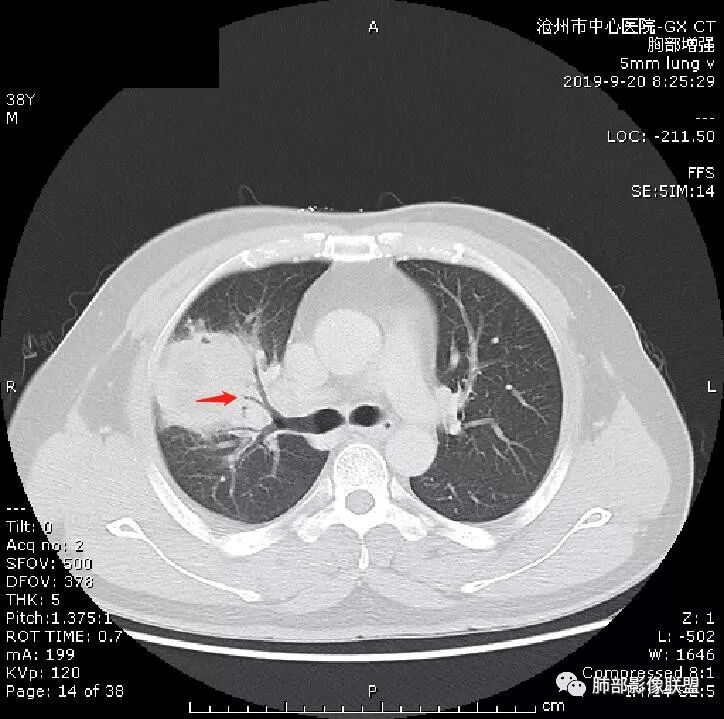

首先病灶示:跨尖、后、前三段,局部突入中叶;大家理解一下:是不是光滑的地方有叶裂,毛糙的地方没叶裂。

这个病变两侧受叶裂的局限,中央没有,如果是穿透叶裂的是否边缘也毛糙?事实上这叶裂边缘的叶裂是很光滑的,我倾向于这个是局部叶裂有缺陷;就是从缺陷处进来有病灶的本色:边缘毛糙;附近叶裂的阻挡,边缘光滑;既然怀疑是局部的缺陷就对良恶性没价值。

中央太突兀了,有道理;如果恶性侵犯也不会这么突兀,所以可能是有缺陷或薄弱的地方;

恶性侵犯,整体都会毛糙

对,这个病灶周围胸膜没有膨隆或占位效应,会不会病变以收缩为主;如果有缺陷,这种良恶性都可以,两侧胸膜没有膨隆,也不能说排除恶性;如果膨隆,恶性可能性大,但是也可以被阻挡。

跨叶病灶有很多种思路,跨叶的病灶多是炎性的,炎性病变沿着胸膜直接蔓延到对侧;恶性肿瘤也有,但是不多,相对比例低,但是恶性肿瘤目前的观点,有两大派:

第一种有直接侵犯过去的;叶间胸膜有2层脏层胸膜,间隔胸膜腔,侵及对侧常会形成胸水,胸膜或多或少都有改变。

第二种是局部叶裂畸形或发育不全、有缺陷,病灶经缺陷处侵犯蔓延,事实上叶裂缺并非少见,影像观察应当结合冠矢状位。

假如一个病灶直接跨越胸膜侵犯过来,应该边缘都很毛糙,不应该是最突出的地方毛糙,应该是逐步毛糙过去的,充其量越到外面毛糙越少;但事实上今天这个病变是一个很突兀的毛糙,突然间嘎然而止的毛糙;所以这个提示应该是从缺陷处跨过来的;还有今天的这个病例,病灶跨叶的部分对附近的胸膜是推移的,附近的胸膜还是很光滑,但是跨叶的病灶区很毛糙,提示跨叶部分存在胸膜缺陷可能;一般来说恶性肿瘤直接侵犯到对侧还是少的,如果这个地方你怀疑有缺陷,跨胸膜在诊断良恶性价值就不大了。